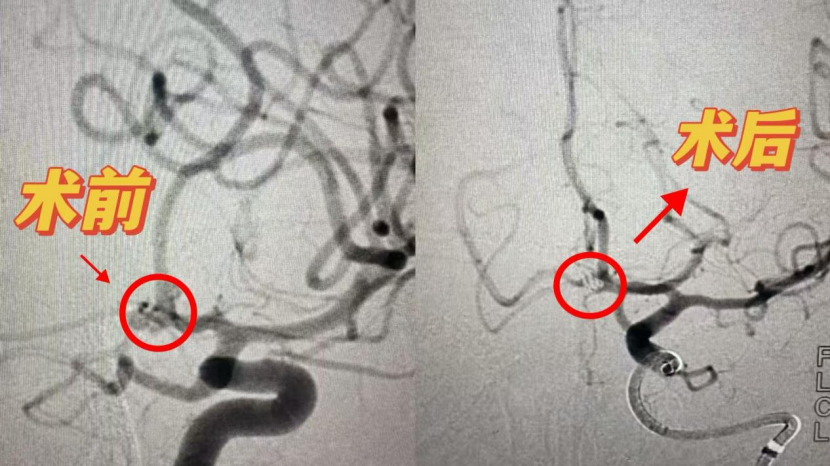

时间就是生命,刻不容缓。郭晓宾主任团队当机立断,在全麻下为患者施行了颅内动脉瘤弹簧圈栓塞术。手术过程顺利,成功封堵破裂动脉瘤,阻断出血源头,为后续康复奠定了关键基础。由于患者出血量相对较多,术后团队又及时实施腰大池引流术,以减轻脑脊液压力、促进积血吸收,防止继发性脑损害。目前,患者仍在密切监护与康复之中,生命体征平稳,神经功能逐步恢复。

郭晓宾主任介绍,颅内动脉瘤破裂引起的蛛网膜下腔出血起病急、病情凶险,如不及时处理,可导致严重残疾甚至死亡。弹簧圈栓塞术是一种神经介入微创技术,通过导管将柔软金属弹簧圈送入动脉瘤腔内,促使其形成血栓并隔绝血流冲击,从而有效降低再出血风险,创伤小、恢复快。